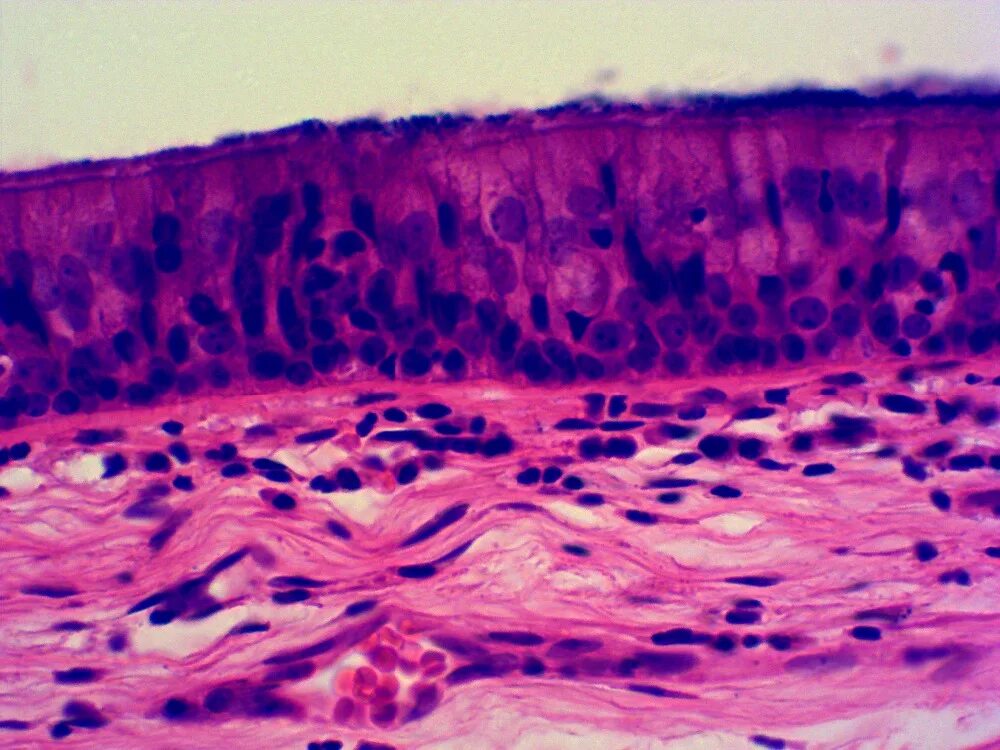

Гистология изучение